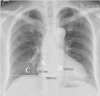

The present study aimed to investigate the association between cardiothoracic ratio (CTR) and left ventricular (LV) systolic function parameters in patients with or without preserved LV ejection fraction (LVEF). A total of 203 subjects suspected with coronary artery disease underwent chest radiography and dual source computed tomography coronary angiography (DSCT-CA). The LV systolic function parameters: LV end-diastolic volume index (LVEDVI), LV end-systolic volume index (LVESVI), and LVEF were measured from the DSCT-CA. The association between CTR and LV systolic function parameters was analyzed according to LVEF value (<55%, depressed LVEF group; versus ≥55%, preserved LVEF group) and CTR value (<0.5, normal range CTR group; versus ≥0.5, larger CTR group). The LVEDVI and LVESVI were higher in the depressed LVEF group compared with the preserved LVEF group (108.56±57.15 vs. 67.52±14.56 ml/m2, P<0.001; and 64.07±37.81 vs. 20.23±7.23 ml/m2, P<0.001, respectively) and lower in the normal range CTR group compared with the larger CTR group (67.10±15.00 vs. 77.30±34.32 ml/m2, P=0.009 and 21.94±8.96 vs. 28.97±26.54 ml/m2, P=0.017, respectively). Significant correlations were found between CTR and LVEDVI, and LVESVI and LVEF in the depressed LVEF group (r=0.66, P<0.001; r=0.65, P<0.001; and r=-0.46, P=0.018, respectively). However, there was no significant association detected between CTR and LV systolic function parameters in the other subgroups. The LVEDVI and LVESVI showed an inverse correlation with the LVEF in each group. Although the CTR was not a reliable indicator of LV size and systolic function in patients with preserved LVEF, it was correlated with LV size and LVEF in patients with depressed LVEF.